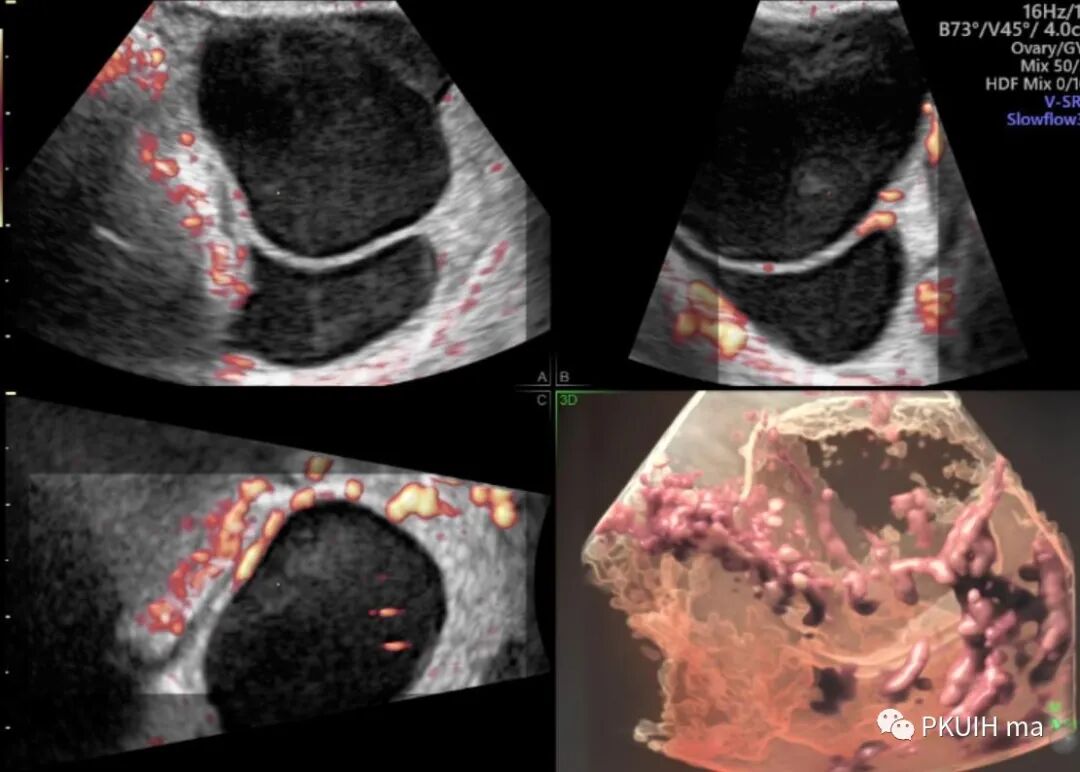

同样我们可以利用容积血流成像来显示颅底动脉环,看着更有立体感,但效果不如SlowFlow功能

同样我们可以把这个功能用在妇科方面,评估内膜血流情况,可以借助三维来对内膜血流分级。

还有也可以借助此功能来观察卵巢肿物内的血流,对鉴别良恶性及囊实性有一定帮助。